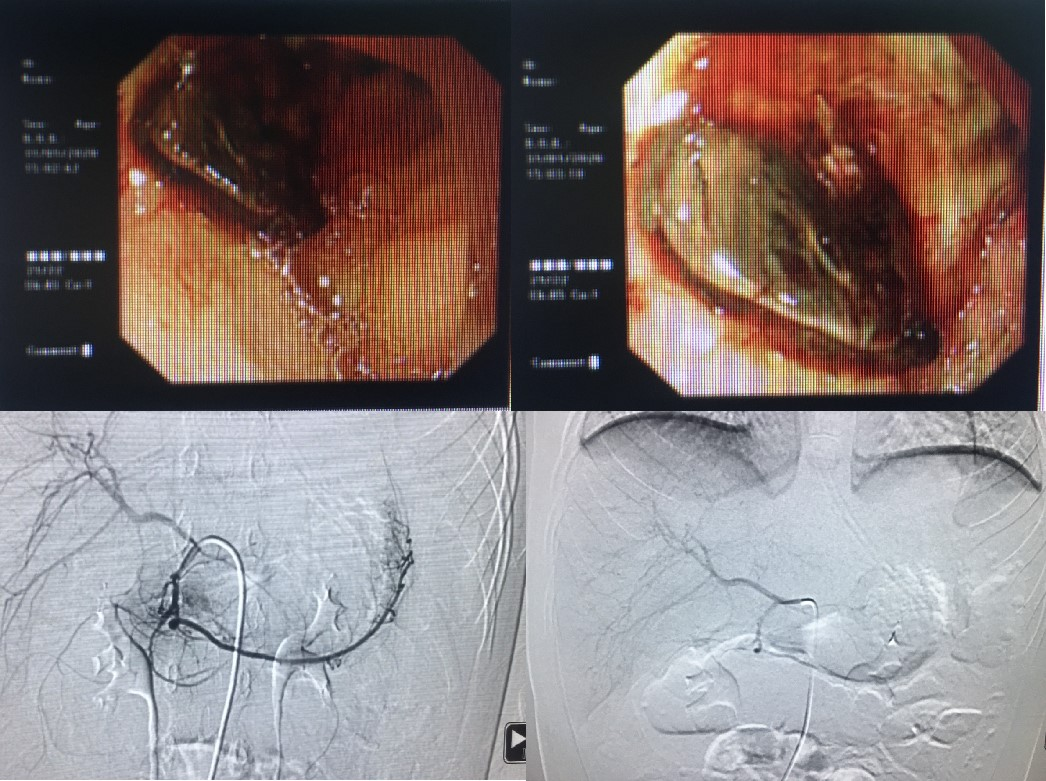

咯血经导管动脉栓塞后造影畸形血管消失

呕血

呕血(hematemesis)指患儿呕吐血液,消化道出血所致。在确定呕血之前,必须排除口腔、鼻、咽喉等部位的出血以及咯血。应针对病因治疗,一般先采用内科保守治疗,内科保守治疗无效后,建议行经导管动脉栓塞治疗。

十二指肠溃疡导致大量呕血后经导管动脉栓塞治疗后完全止血。